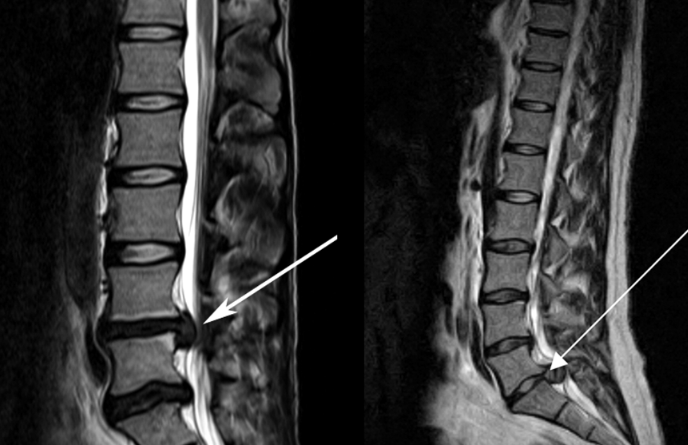

![]() 關(guān)于腰椎間盤突出 ![]() 腰椎間盤突出癥是纖維環(huán)破裂后髓核突出壓迫神經(jīng)根造成以腰腿痛為主要表現(xiàn)的疾病。腰椎間盤退行性改變或外傷所致纖維環(huán)破裂,髓核從破裂處脫出,壓迫腰椎神經(jīng),從而出現(xiàn)腰腿放射性疼痛。 ![]() 病因: 一、退行性變: 目前認(rèn)為,其基本病因是腰椎間盤的退行性變。退行性變是一切生物生、長(zhǎng)、衰、亡的客觀規(guī)律,由于腰椎所承擔(dān)的特殊的生理功能,腰椎間盤的退行性變比 其他組織器官要早,而且進(jìn)展相對(duì)要快。這個(gè)過程是一個(gè)長(zhǎng)期,復(fù)雜的過程。所謂腰椎間盤退行性改變:即由于椎間盤受體重的壓迫,加上腰部又經(jīng)常進(jìn)行彎曲、后伸等活動(dòng),易造成椎間盤的擠壓和磨損,尤其是下腰部的椎間盤,從而產(chǎn)生退行性改變。腰椎間盤退行性改變是本病發(fā)生的基礎(chǔ)。 二、其他因素: 1、外力作用:在日常生活和工作中,部分人往往存在長(zhǎng)期腰部用力不當(dāng)、過度用力姿勢(shì)或體位的不正確等情況。例如長(zhǎng)期從事彎腰工作的煤礦工人和建筑工人需經(jīng)常彎腰提舉重物。這些長(zhǎng)期反復(fù)的外力造成的損傷日積月累地作用于椎間盤,加重了退變的程度。 2、椎間盤自身解剖因素的弱點(diǎn): (1) 椎間盤在成人之后逐漸缺乏血液循環(huán),修復(fù)能力也較差,特別是在退變產(chǎn)生后,修復(fù)能力更加微弱。 (2) 椎間盤后外側(cè)的纖維環(huán)較為薄弱,而后縱韌帶在腰5、骶1平面時(shí)寬度顯著減少,對(duì)纖維環(huán)的加強(qiáng)作用明顯減弱。 (3) 腰骶段先天異常:腰骶段畸形可使發(fā)病率增高,這些異常造成椎間隙寬度不等,并常造成關(guān)節(jié)突出,關(guān)節(jié)受到更多的旋轉(zhuǎn)勞損,使纖維環(huán)受到的壓力不一,加速退變。 3、種族、遺傳因素:有色人種發(fā)病率較低,例如印第安人和非洲黑人等發(fā)病率較其他民族明顯要低。 ![]() 2 病理 腰椎間盤突出癥的病理變化過程大致可分為三個(gè)階段: 1、突出前期:髓核因退變和損傷可變成碎塊狀物,或呈瘢痕樣結(jié)締組織,變性的纖維環(huán)可因反復(fù)損傷而變薄變軟或產(chǎn)生裂隙。此期病人可有腰部不適或疼痛,但無放射性下肢痛。也有的人原無病變,可因一次大的暴力引起髓核突出。 2、突出期:外傷或正常的活動(dòng)使椎間盤壓力增加時(shí),髓核從纖維環(huán)薄弱處或破裂處突出。突出物刺激或壓迫神經(jīng)根即發(fā)生放射性下肢痛,或壓迫馬尾神經(jīng)發(fā)生大小便功能障礙。在老 年患者,可因椎間盤退變,整個(gè)纖維環(huán)變得軟弱松弛,椎間盤可呈彌漫性向周圍膨出。 3、突出晚期:腰椎間盤突出后,病程較長(zhǎng)者,椎間盤本身和其他鄰近結(jié)構(gòu)均可發(fā)生各種繼發(fā)性病理改變。 3 誘發(fā)因素 腰椎間盤突出癥的基本因素是椎間盤退變,但某些誘發(fā)因素可致使椎間隙壓力增高,引起髓核突出。此種誘發(fā)因素常與以下因素有關(guān): 1. 年齡因素:腰椎間盤突出癥的好發(fā)年齡在30-50歲,平均手術(shù)年齡在40歲,因此退變可能是其重要因素。 2. 身高與性別:有人認(rèn)為身材過高也會(huì)易發(fā)腰突癥,而男性發(fā)病率是女性的5倍。 3. 增加腹壓:臨床上有約1/3的病人在發(fā)病前有明確的增加腹壓的因素,如劇烈的咳嗽、噴嚏、屏氣、用力排便等。使腹壓增高,破壞了椎節(jié)與椎管之間的平衡狀態(tài)。 4. 不良體位:人在完成各種工作時(shí),需要不斷更換各種體位以緩解腰部壓力,如長(zhǎng)期處于某一體位不變,即可導(dǎo)致局部的累積性損傷。特別是長(zhǎng)期處于不良姿勢(shì)更容易誘發(fā)本病。 5. 職業(yè)因素:重體力勞動(dòng)者發(fā)病率最高,白領(lǐng)勞動(dòng)者最低。汽車駕駛員由于長(zhǎng)期處于顛簸和振動(dòng)狀態(tài),椎間盤承受的壓力大且反復(fù)變化,也易誘發(fā)椎間盤突出。 6. 受寒受濕:寒冷或潮濕可引起小血管收縮、肌肉痙攣,使椎間盤的壓力增加,可能造成退變的椎間盤破裂。 ![]() ![]() ![]() ![]() 癥狀: 腰椎間盤突出癥患者最多見的癥狀為疼痛,可表現(xiàn)為腰背痛、坐骨神經(jīng)痛,典型的坐骨神經(jīng)痛表現(xiàn)為由臀部、大腿后側(cè)、小腿外側(cè)至跟部或足背的放射痛。據(jù)臨床統(tǒng)計(jì),約95%的腰突癥患者有不同程度的腰痛,80%的患者有下肢痛。特別是腰痛,不僅是腰椎間盤突出最常見的癥狀,也是最早出現(xiàn)的癥狀之一。 ![]() ![]() ![]() 檢查: 1、X線:腰椎間盤所包括的髓核、纖維環(huán)和軟骨板密度均較低,在X線下并不顯影,因此臨床上腰突癥患者的腰椎X線平片可僅有一些非特異性的變化,甚至無異常變化。因此單純腰椎平片并不能作為有無腰椎間盤突出癥的直接依據(jù),但X線能發(fā)現(xiàn)腰椎的退行性改變和結(jié)構(gòu)異常,對(duì)提示椎間盤的退變有重要意義,并且能排除其他的一些腰椎疾患,如腰椎結(jié)核、腫瘤和腰椎滑脫等。典型的腰椎間盤突出癥患者通過病史、體征和X線平片即能作出初步的診斷。 2、CT檢查:腰椎的CT可以清楚地顯示椎間盤突出的部位、大小、形態(tài)和神經(jīng)根、硬脊膜受壓的情況,同時(shí)還可顯示黃韌帶肥厚、小關(guān)節(jié)增生、椎管和側(cè)隱窩狹窄等情況。對(duì)腰椎間盤突出癥診斷的準(zhǔn)確率達(dá)到80%-92%。 3、核磁共振(MRI):核磁共振沒有輻射,可以多方位成像(橫斷面、冠狀面、矢狀面和斜面),對(duì)解剖細(xì)節(jié)顯示較好,對(duì)組織結(jié)構(gòu)的細(xì)微病理變化更敏感(如骨髓的浸潤(rùn)),可以排除神經(jīng)和脊柱腫瘤等。對(duì)于一些落到椎管的髓核組織也不會(huì)遺漏。 4、脊髓造影:脊髓造影利用椎管內(nèi)蛛網(wǎng)膜下腔的空隙,注入造影劑后在X線下攝片,顯示椎管內(nèi)部結(jié)構(gòu)。目前常用水溶性造影劑,能較清晰地顯示硬膜腔、馬尾神經(jīng)和神經(jīng)根鞘,對(duì)腰椎間盤突出癥的診斷可達(dá)90%左右,主要X線表現(xiàn)為硬膜囊壓迫征象和神經(jīng)根鞘壓迫征象。但由于CT和MRI在臨床的廣泛應(yīng)用,無創(chuàng)傷且診斷率更高,脊髓造影在臨床上的應(yīng)用已經(jīng)大大減少,而且由于它副作用較大,甚至可能造成截癱等嚴(yán)重情況,目前主張慎重選用。 5、肌電圖:肌電圖是對(duì)周圍神經(jīng)與肌肉的電生理檢查方法,可用于觀察并記錄肌肉在靜止、主動(dòng)收縮和支配其的周圍神經(jīng)受刺激時(shí)的電活動(dòng),同時(shí)也可用來測(cè)量周圍神經(jīng)的傳導(dǎo)速度。在腰椎間盤突出癥上,肌電圖主要通過檢查雙下肢肌肉的興奮性來反映相應(yīng)神經(jīng)根的狀態(tài),并根據(jù)異常電活動(dòng)的分布范圍來判斷椎間盤突出和神經(jīng)根受壓的節(jié)段。在脊神經(jīng)根和馬尾神經(jīng)受壓的病人,肌電圖陽性率可達(dá)80%-90%,但與CT和MRI相比并不是首選的檢查手段,可用于輔助診斷和判斷神經(jīng)根的受壓情況,同時(shí)也可以用來作為判斷治療后神經(jīng)根恢復(fù)情況的指標(biāo)之一。 ![]() ![]() ![]() 預(yù)防: 腰椎間盤突出癥是在退行性變基礎(chǔ)上積累傷所致,積累傷又會(huì)加重椎間盤的退變,因此預(yù)防的重點(diǎn)在于減少積累傷。 日常注意事項(xiàng): 1.平時(shí)要有良好的坐姿,睡眠時(shí)的床不宜太軟。 2.長(zhǎng)期伏案工作者需要注意桌、椅高度,定期改變姿勢(shì)。 3.職業(yè)工作中需要常彎腰動(dòng)作者,應(yīng)定時(shí)伸腰、挺胸活動(dòng),并使用寬的腰帶。 4.應(yīng)加強(qiáng)腰背肌訓(xùn)練,增加脊柱的內(nèi)在穩(wěn)定性,長(zhǎng)期使用腰圍者,尤其需要注意腰背肌鍛煉,以防止失用性肌肉萎縮帶來不良后果。 5.如需彎腰取物,最好采用屈髖、屈膝下蹲方式,減少對(duì)腰椎間盤后方的壓力。 ![]() ![]() ![]() 治療: (一)中醫(yī)外敷療法: 腰椎間盤突出可以外貼 腰突正骨膏,其有效成分可透入皮膚產(chǎn)生活血,止痛,化淤,通經(jīng)走絡(luò),開竅透骨,祛風(fēng)散寒等效果,并通過藥物的歸經(jīng)作用而調(diào)理機(jī)體陰陽平衡,滲透于表皮,刺激神經(jīng)末梢,促進(jìn)局部血液微循環(huán),扶正固本、改善體質(zhì),從根本上、全方位針對(duì)腰椎疾病病機(jī)特點(diǎn)而發(fā)揮療效,改善病變周圍組織營(yíng)養(yǎng),起到修復(fù)骨病組織的作用,最終達(dá)到治療目的。 (二)自我治療: 1.腹肌鍛煉: 也就是仰臥起坐。每次做十個(gè),每天三次。(可根據(jù)患者的體質(zhì)來定,不可逞強(qiáng))。 2.交叉扭腰: 兩腳分開與肩寬,腳尖向內(nèi)兩臂伸直,一手在體側(cè),一 手舉過頭頂。如果右手在上,先向左側(cè)后方擺。左側(cè)相反。于此同時(shí)腰部也隨之扭動(dòng),左右各100次。 3.抱膝觸胸: 處于仰臥位,雙膝屈曲,手抱住膝部,使盡量靠近胸部,然后放下,一上一下為一個(gè)動(dòng)作,可持續(xù)30個(gè)。 4.腰背肌鍛煉: 處于平臥,雙膝彎曲放在床上,然后用力將臀部抬起,離開床面10厘米。這時(shí)您會(huì)感覺到腰背部在用力,堅(jiān)持5秒鐘,反復(fù)10下。 ![]() (三)非手術(shù)治療: 非手術(shù)療法是治療腰椎間盤突出癥的基本療法,約80%以上的患者經(jīng)保守治療均可得到緩解和痊愈。其主要療法有: 1.日常家庭治療:早期腰椎間盤突出癥,癥狀輕微,不需要做特殊的治療。第一,注意臥床休息,避免腰椎受外力壓迫,第二,應(yīng)用其他方法積極鍛煉腰部肌肉力量。 2.牽引治療; 3.推拿按摩治療; 4.物理治療; 5.消炎鎮(zhèn)痛藥物; 6.減輕神經(jīng)根水腫藥物。 (四)推拿治療: 1.解除腰臀部肌肉痙攣 2.拉寬椎間隙,降低盤間壓力 3.增加椎間盤外壓力 4.調(diào)整后關(guān)節(jié),松解粘連 5.促使受損傷的神經(jīng)根恢復(fù)功能 (五)微創(chuàng)治療: 微創(chuàng)治療方法的目的是消除腰椎間盤突出的髓核以解除對(duì)神經(jīng)的壓迫。微創(chuàng)治療技術(shù)采用可視設(shè)備,創(chuàng)口不足一厘米有些甚至不足一毫米。消融或摘除髓核,從根本上解除致病因素,因而能夠取得很好的效果。 (六)手術(shù)治療: 腰椎間盤突出癥的手術(shù)原則是嚴(yán)格無菌操作,盡量保留不必去除的骨結(jié)構(gòu)和軟組織結(jié)構(gòu),以最小的創(chuàng)傷達(dá)到足夠的顯露,仔細(xì)徹底地去除病變組織,達(dá)到治療目的。 ![]() ![]() 綠柏相關(guān)產(chǎn)品: ![]() 懸吊訓(xùn)練療法是康復(fù)醫(yī)學(xué)中以持久改善肌肉骨骼疾病為目的的,應(yīng)用主動(dòng)治療和訓(xùn)練的一個(gè)總的概念整合,是一種運(yùn)動(dòng)感覺的綜合訓(xùn)練系統(tǒng),包括診斷與治療兩大系統(tǒng)。 產(chǎn)品特點(diǎn): 1.電腦軟件管理系統(tǒng),涵蓋患者信息管理、評(píng)估、訓(xùn)練、量表、報(bào)告、視頻教學(xué)六大模塊,輕松實(shí)現(xiàn)評(píng)估與訓(xùn)練一體化管理; 2.多點(diǎn)多軸設(shè)計(jì),滿足不同治療方案設(shè)計(jì); 3.懸吊工作站及各個(gè)懸吊點(diǎn),均能實(shí)現(xiàn)任意位置移動(dòng),一鍵解鎖,省時(shí)省力; 4.實(shí)時(shí)力反饋,精準(zhǔn)量化弱鏈測(cè)試及懸吊治療全過程,給治療師及患者最直觀的效果呈現(xiàn); 5.智能神經(jīng)肌肉促通裝置,可根據(jù)評(píng)估結(jié)果設(shè)置治療模式、頻率、時(shí)間等相關(guān)參數(shù),讓懸吊康復(fù)更加高效有針對(duì)性; 6.外觀高端大氣,結(jié)構(gòu)穩(wěn)固,給患者安全保障,增加治療信心。 ![]() |